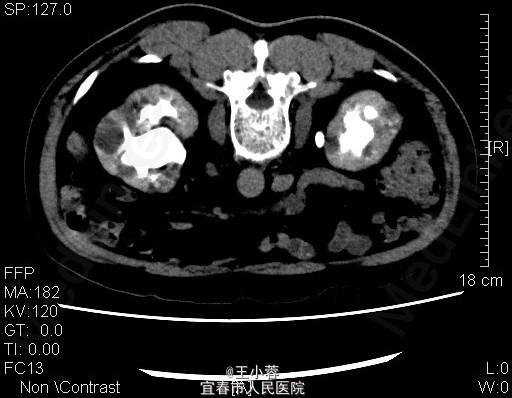

3、查体:未见明显异常 4、辅助检查:当地人民医院泌尿系彩超示:双肾多发结石(未见报告),我院肌酐124.2umol/L,糖6.62mmol/L。我院双肾CTU:1、双肾铸型结石,双肾中度积液,双肾功能减低;腹膜后多发稍大淋巴结。2、多囊肝,多囊肾,双肾多发复杂性囊肿。3、慢性胆囊炎。4、腹主动脉及双侧髂动脉硬化